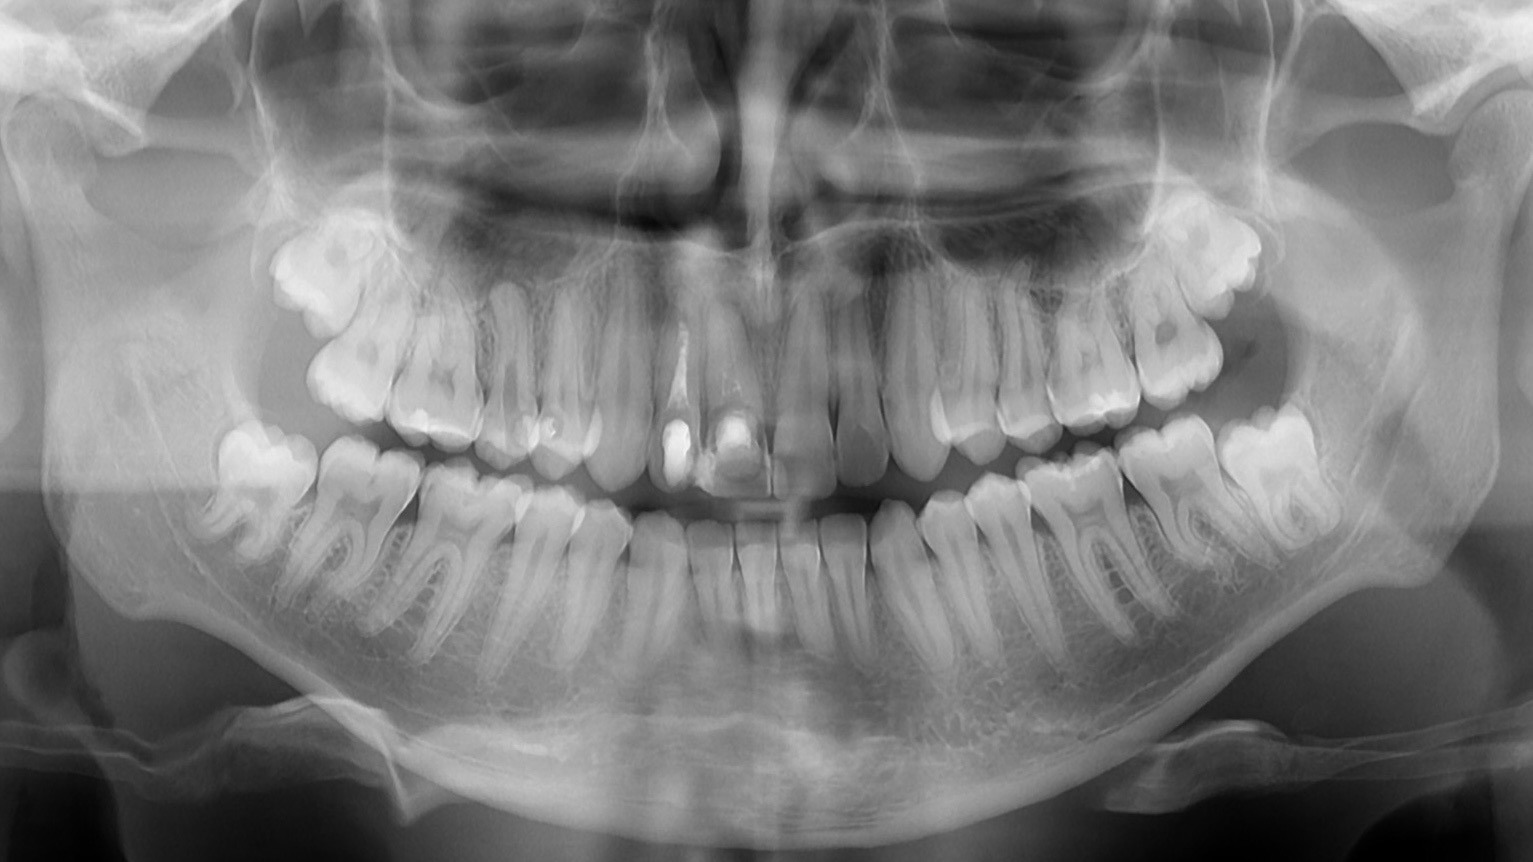

The poster provided a clear and structured overview of the pre-, intra-, and postoperative stages of ceramic implant placement, illustrating:

the biological reasoning behind treatment decisions,

the dynamics of soft- and hard-tissue healing,

and the long-term functional and aesthetic outcomes achievable with ceramic implants.